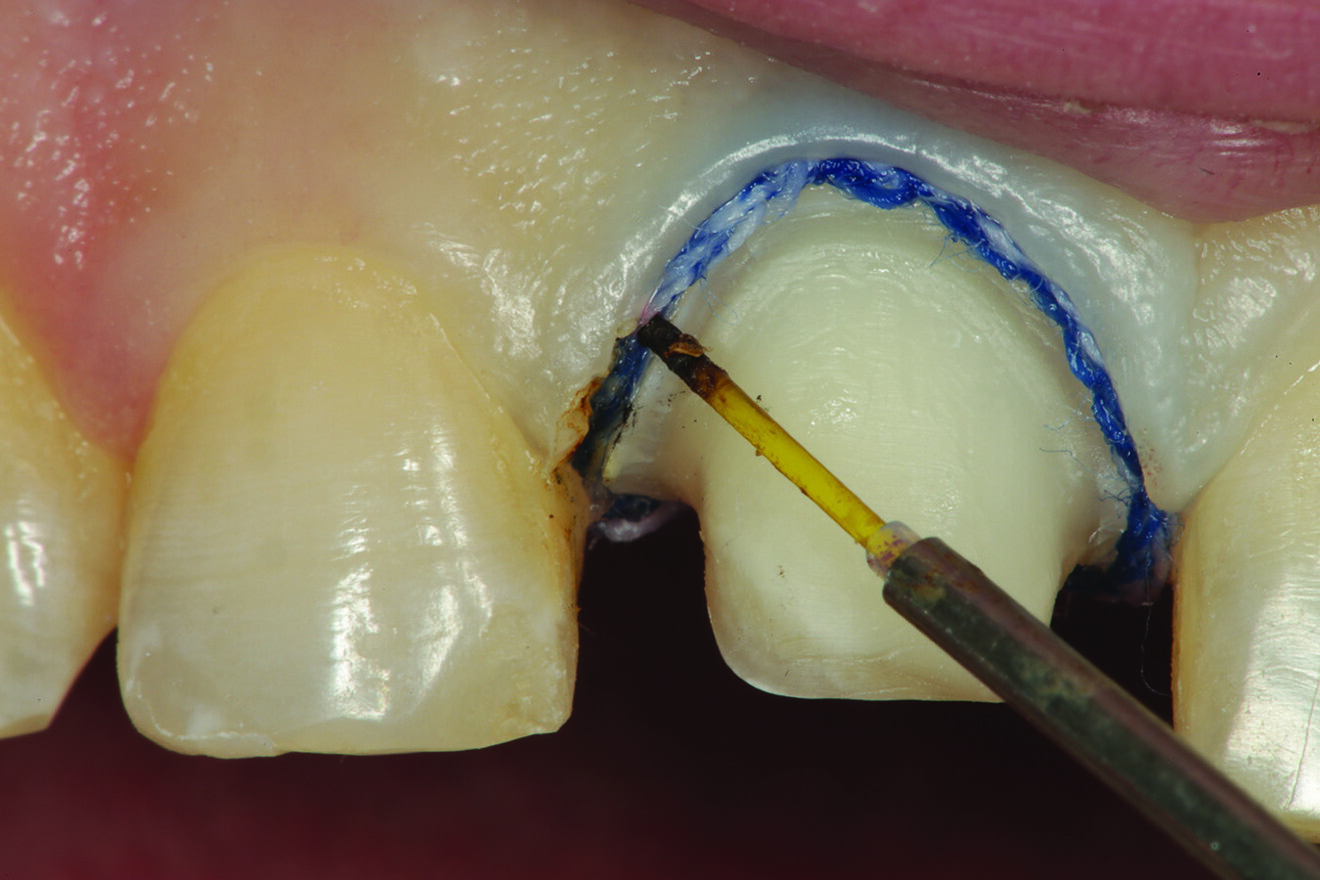

In this case, after placement of the #1 retraction cord, there was excess tissue in the facial area of the preparation that may have interfered with the light-bodied impression material flowing subgingivally. A super-pulsed diode laser (Gemini, Ultradent Products) was used to meticulously remove the excess tissue incisal to the cord without damaging the cord (Figs. 12 & 13). The retraction cord was entirely visible before removal, allowing unimpeded access for the light-bodied impression material to flow into the retracted area.

Fig. 12: Using a super-pulsed diode laser to remove the excess tissue incisal to the top cord.